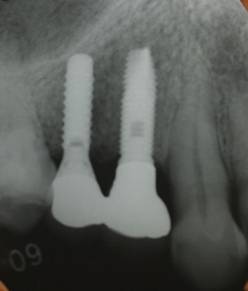

ストローマンインプラントとスプラインインプラント

術前

ストローマンインプラントとスプラインインプラントが隣り合わせに埋入されています.このころストローマンからスプラインに変えています。変えた理由は前歯部の審美性に優れていること、アバットメントの自由度があること、抜歯後すぐに埋入できるなどでした。